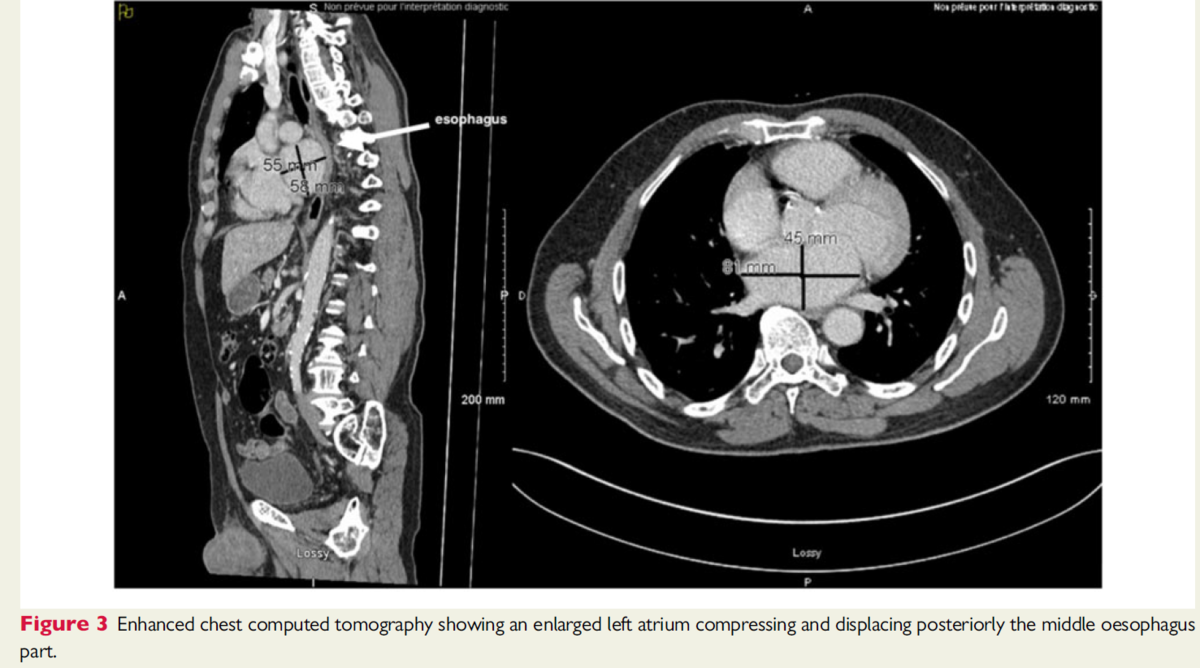

胸部造影CTは巨大な左心房が食道中部を後方へ移動させており、中部食道を圧迫していることを明らかにした。

胸部造影CTにおいて、前後径81mm,横径45mmの巨大な左心房が食道中部を後方に圧迫し移動させていることが明らかになった。(図3)